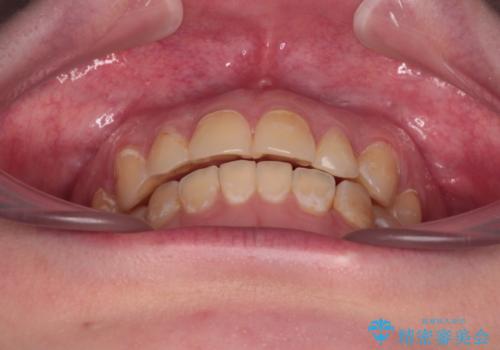

舌側転位している側切歯特有の、切縁の位置が不揃いであったり、根元が内側に引っ込んだ状態であったりという、インビザライン独特の仕上がりになることなく、きれいに整った歯列とすることができました。

- 前歯のデコボコとクロスバイトが気になり、インビザラインによる矯正治療を希望して来院された患者様です。

上顎側切歯(上の真ん中から2番目の歯)が舌側転位している場合、無理して動かそうとすると歯髄壊死を起こすリスクが高い印象があります。

インビザライン単体でも治療は可能ですが、安全策としてインビザラインで歯列を移動する前に上顎前歯をワイヤー矯正で整え、その後上下歯列をインビザラインにて矯正治療を行うこととしました。